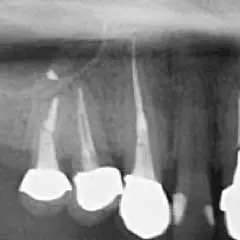

一般のレントゲンでは確認できない部位までも可視化するCT装置

CTはマイクロスコープ(歯科用顕微鏡)同様、治療部位を「見える化」させる機器です。通常のレントゲン(デンタルエックス線写真)でも大まかには判断可能ですが、CTを用いる事で、デンタルエックス線写真では発見できないような微細な病変も発見することが出来ます。

CT画像

レントゲン画像